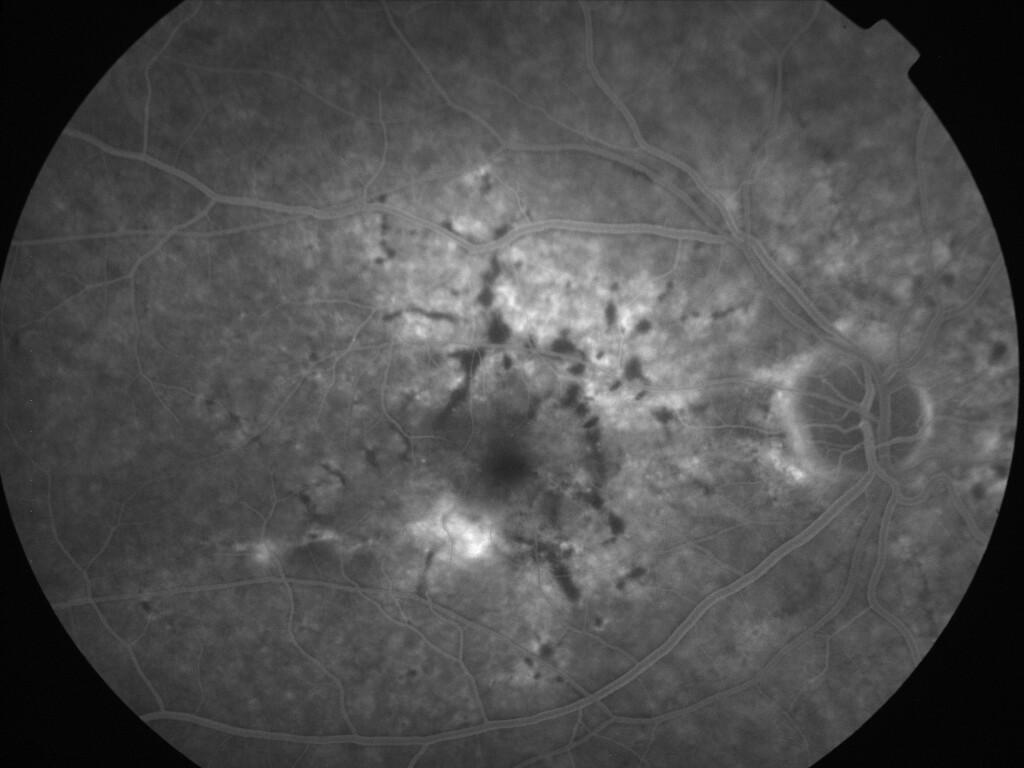

ASSOCIATION STRIES ANGIOIDES ET DYSROPHIE MACULAIRE RETICULEE

NEOVASCULARISATION